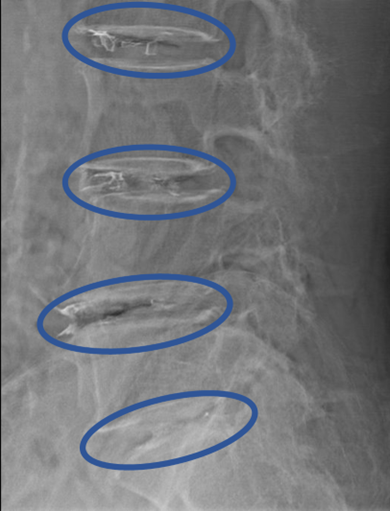

DiscoGelを入れた後の画像になります。

治療は 40分程度で終了

回復室で休憩後、歩いて帰院されました。